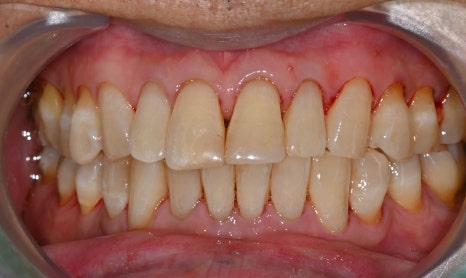

▼ 아래는 본원에서 치료한 실제 스케일링 전후 사진입니다.

-치료 전

왼쪽 사진: 병원에 첫 내원하셨을때 촬영한 구강 정면사진입니다.

- 치료 후

왼쪽 사진: 치석 제거 후 잇몸선이 깔끔하게 정리되며 구강 위생 개선 되었습니다.